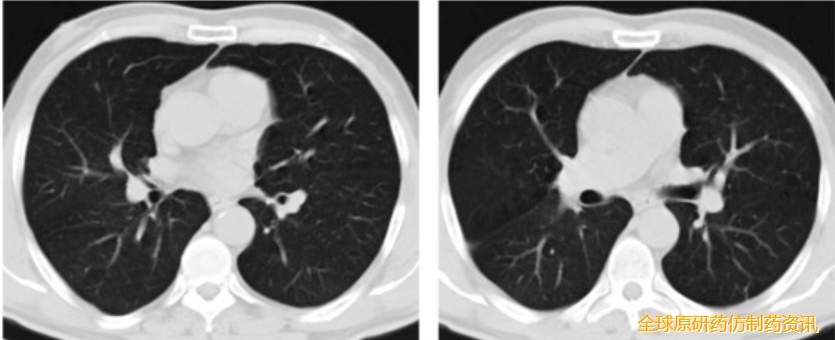

4周化疗后双肺后部肿块完全消失,随后接受肺癌疫苗治疗,持续完全缓解长达8年

这位幸运的患者既往接受三线化疗和放疗均失败,但在使用 Neo-DCVac 后 7.6 个月内未出现任何疾病进展迹象。在五剂个性化Neo -DCVac 免疫治疗之前和之后进行 CT 扫描显示肿瘤靶病灶显著消退。

这位患者同样也经历三线化疗、放疗和 PD-1 抑制剂治疗失败,在 Neo-DCVac 治疗后,肿瘤靶病灶缩小了 29%。